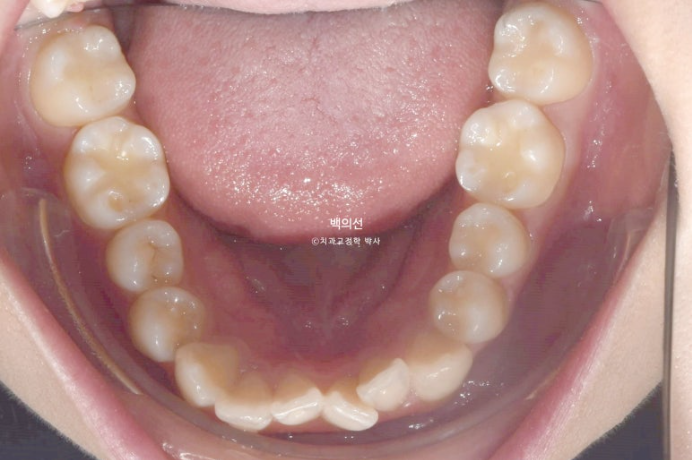

23.05